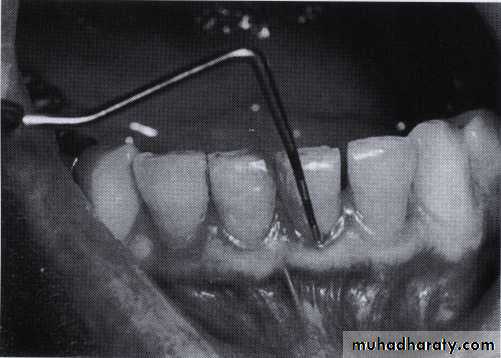

• Extrusion of the maxillary left central incisor and diastema

• associated with a periodontal pocket• Deep periodontal pocket revealed by probing. The probe has penetrated to its entire length.

• The probe should be inserted parallel to the vertical axis of the tooth and "walked" circumferentially around each surface of each tooth to detect the areas of deepest penetration• "Walking" the probe to explore the entire pocket.

• Special attention should be directed to detecting the presence of• interdental craters and furcation involvements

• To detect an interdental crater, the probe should be placed obliquely from both the facial and lingual surfaces so as to explore the deepest point of the pocket located beneath the contact point

• Vertical insertion of the probe (left) may not detect interdental craters; oblique positioning of the probe (right) reaches

• the depth of the crater.